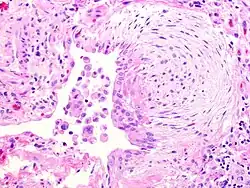

O fibroblasto é a célula constituinte do tecido conjuntivo e sua função é formar a substância fundamental amorfa. Tem um citoplasma ramificado e rodeado de um núcleo elíptico contendo 1-2 nucléolos. Os fibroblastos ativos podem ser reconhecidos pela abundante ocorrência de retículo endoplasmático. Amadurece, transformando-se em um fibrócito. É responsável pela biossíntese de colágeno do tipo 1. Produz substância intercelular e origina células de outros tecidos conjuntivos, são responsáveis pela regeneração.

Os fibroblastos sintetizam as proteínas colágeno e elastina, além das glicosaminoglicanas e glicoproteínas multiadesivas que farão parte da matriz extracelular. Essas células estão também envolvidas na produção de fatores de crescimento, que controlam o crescimento e a diferenciação celular. Os fibroblastos são as células mais comuns do tecido conjuntivo e são capazes de modular sua capacidade metabólica, a qual vai refletir em sua morfologia. As células com intensa atividade de síntese são denominadas de fibroblastos, enquanto as células metabolicamente quiescentes são conhecidas como fibrócitos.